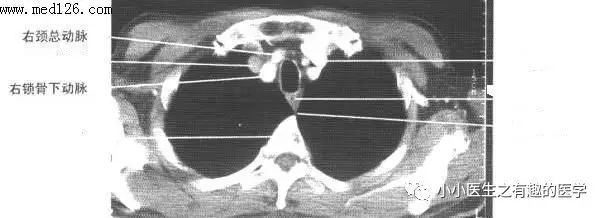

最下边的是锁骨下动脉,锁骨下动脉上边的是颈总动脉。